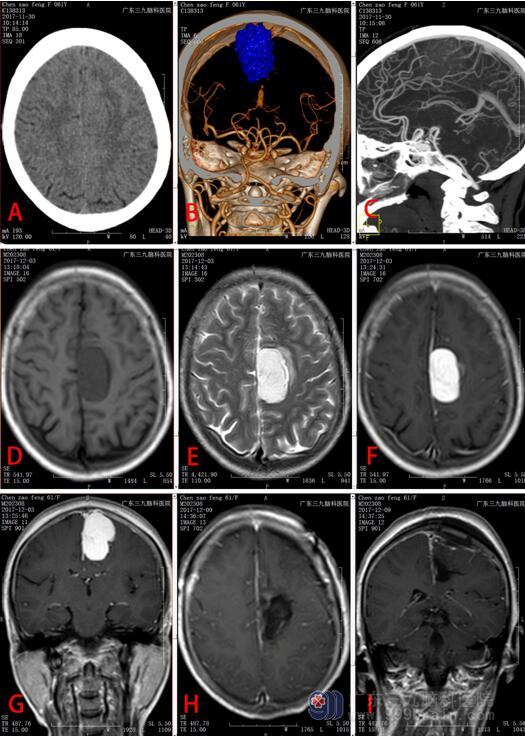

患者于2017年11月29日就诊我院,61岁女性,主诉为“头晕、头痛伴右侧肢体乏力1月”。入院时查体:左侧肌力5级,右侧肢体肌力4级,肌张力正常,全身深浅感觉体查未见异常,余神经专科查体未见明显异常。入院后行头颅CT。头颅MR平扫+增强,结果提示:左侧额顶部镰旁占位性病变,考虑脑膜瘤(血管瘤型可能)。术前诊断:左侧额顶部镰旁占位,大小约4.0 ×3.7×2.6cm,脑膜瘤可能(图1所示)。于2017年12月在全麻下行占位切除术。术中电凝离断多支肿瘤的供血动脉,肿瘤质地大部分偏硬,内见纤维及大量钙化改变,血运丰富,大部分边界清楚。肿瘤起始于中部1/3大脑镰,并且已压迫矢状窦。显微镜下肿瘤全切除(图2)。术后病理描述:(左侧中央区)组织,硬膜组织内可见弥漫增生的肿瘤细胞,为卵圆形或短梭形细胞构成,细胞呈螺旋状排列细胞具有异型性,见少量核分裂像<5个/10HPF,未见坏死间质内见多灶性的淋巴细胞浸润。免疫组化:CD163、CD68、S-100均弥漫(+),CD1a(-),Langerin(-),EMA灶性弱(+),PR个别(+),CD34、SSTR-2、GFAP、Olig-2、Melan-A、HMB-45、CD21、CD23均(-),CK(-/+),Ki-67 15%(+)(图2所示)。病理结果提示:(左侧中央区)硬膜发生的组织细胞源性肿瘤,目前的免疫组化表型支持少见的硬膜指状突细胞肉瘤。术后患者言语欠清晰,右侧肢体肌力仍只有3级,未见新发神经功能障碍。术后复查MRI显示肿瘤全切除。结合其病理表现为恶性肿瘤,告知患者需1个月后返院复查并行放射治疗,但患者由于个人原因未能返院进一步治疗。

该病例的影像学表现和脑膜瘤极为相似,如图1所示。该肿瘤基底较宽,位于左侧中央区大脑镰,未见明显脑膜尾征。综合CT和MR表现,影像科医生和临床医生在术前均认为这是一例普通的镰旁脑膜瘤,考虑血管瘤型。Gregor Hutter报道的大脑镰旁IDCS,该病例在MR可见脑膜尾征且伴有瘤内出血,肿瘤大小约7×5× 6 cm大小。那病例在术前亦出现误诊,考虑出血性脑膜瘤、转移瘤或血管外皮细胞瘤。